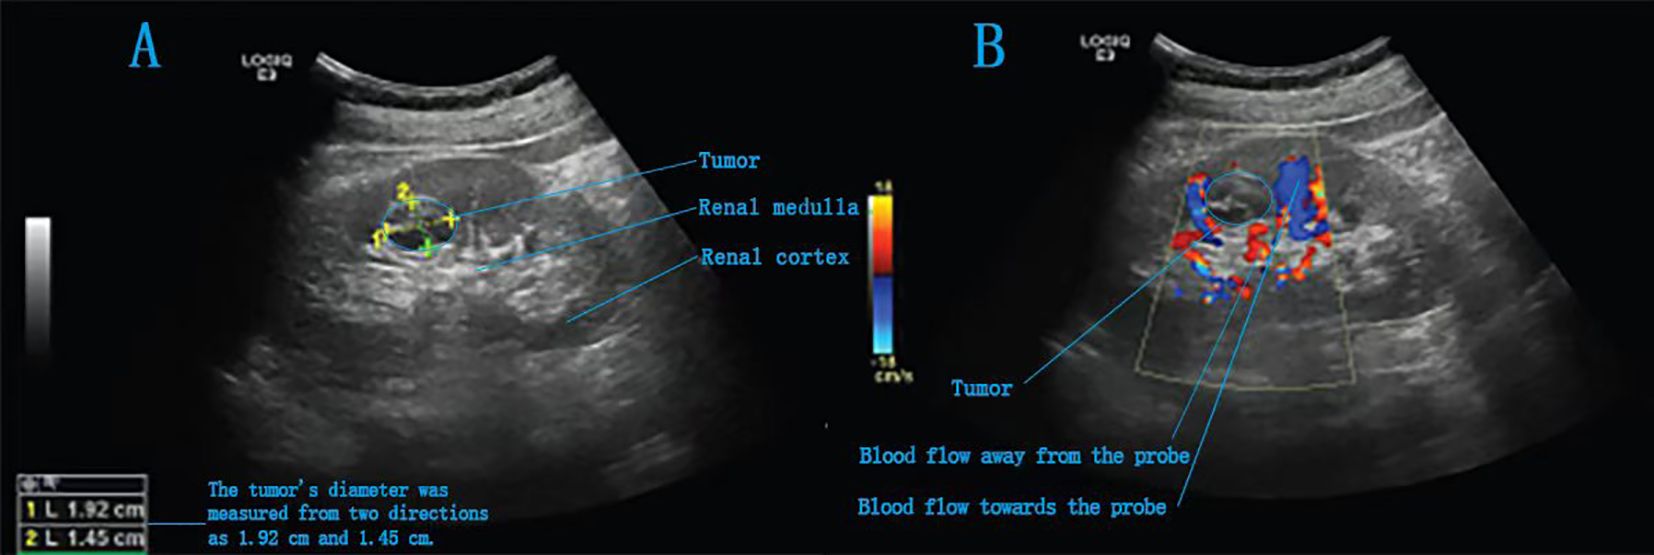

The patient was placed in a 70° lateral decubitus position with the lumbar region elevated. One 5-mm, three 8-mm and two 12-mm trocars were inserted into the abdomen for anchoring the Da Vinci robotic system and assisting the surgical team (Figure 2). For tumour localization, holographic imaging was first used to identify renal artery branches (Figure 3), followed by intraoperative ultrasound confirmation. The ultrasound probe was introduced through a trocar to precisely locate the tumour and delineate its boundaries (Figure 4). Monopolar cautery was used to mark the resection margin on the renal surface. The renal artery was clamped with vascular clips, and the tumour was excised along a line 5 mm outside the ultrasound-marked boundary. For renal reconstruction, the first layer was closed using a 3–0 V-Loc continuous suture for the medulla, and the second layer was closed with a 2–0 V-Loc continuous or locked suture for the capsule. Finally, the tumour specimen was retrieved using forceps, and the surgical site was inspected for active bleeding before removing the trocars and placing a drain. The incision was then closed.

Figure 4. Intraoperative ultrasound images of a completely endogenous renal tumour. (A) A slightly hyperechoic area is detected in the right kidney, with heterogeneous internal echotexture. (B) Intraoperative Doppler ultrasound image.